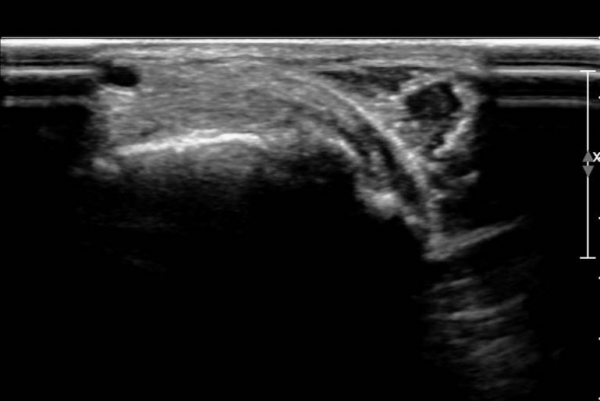

ŽÃËÀÚ¸¦ ¾à°£ ¹ß¹Ù´ÚÃøÀ¸·Î À̵¿ÇÏ´Ï ¼³Çü°ñ ºÎÂøºÎ°ÇÀÇ Àú¿¡ÄÚ º´º¯ÀÌ ¶Ñ·ÈÇÏ´Ù(»çÁø 3, 4).

Àü°æ°ñ°Ç Ⱦ´Ü¸é°Ë»ç¿¡¼­ Á»´õ ¹ß µîÃøÀ¸·Î À§Ä¡ÇÏ´Â Á¦1ÁßÁ·°ñºÎÂøºÎ °ÇÀº °í¿¡ÄÚ·Î Á¤»óÀûÀÎ ¾ç»óÀ¸·Î

°üÂûµÇ³ª Á»´õ ³»Ãø ¹Ù´ÚÃø¿¡ À§Ä¡ÇÏ´Â ¼³Çü°ñ ºÎÂøºÎ °ÇÀÇ Àú¿¡ÄÚ º´º¯ÀÌ °üÂûµÈ´Ù(»çÁø 5,  6).